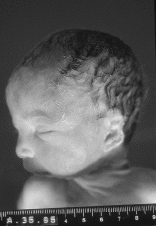

El informe autópsico es el siguiente: Feto hembra de treinta semanas de gestación, según peso y longitudes occipito-sacra y del pie, que presenta inmadurez visceral grado II, polimalformado, presentando anomalías faciales, hipoplasia pulmonar (índice peso corporal/peso pulmonar = 0,007), surco simiesco bilateral, bazo supernumerario (0,3 cm) y quiste simple subcapsular hepático (0,2 cm). Las anomalías faciales son las siguientes: Asimetría del tercio facial inferior, con hipoplasia mandibular y de zigoma derechos, microotia derecha con implantación baja de conducto auditivo externo, discreto hipertelorismo, atresia de coanas bilateral, anquiloglosia y paladar ojival con fisura palatina mucosa (ver imágenes adjuntas).

| Figura 2. |